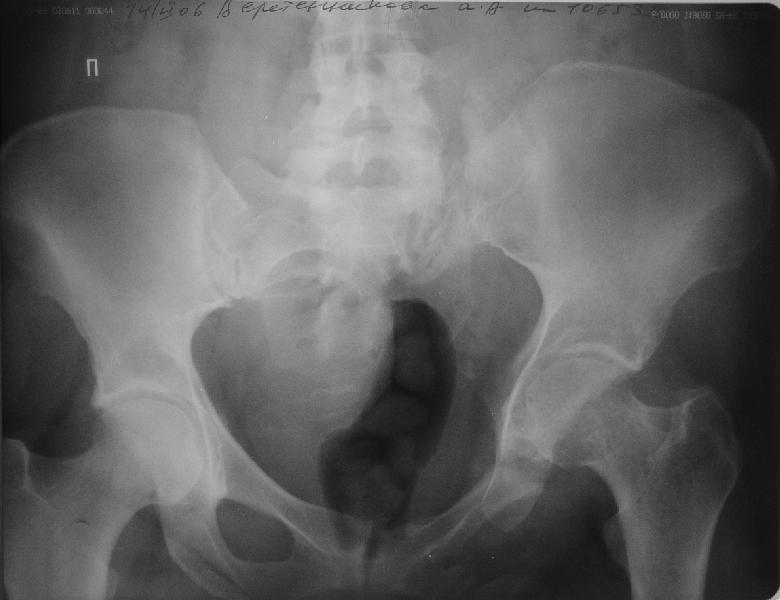

Прооперировали молодую девушку 32 лет спустя 9 мес после травмы.

Имелся стойкий болевой синдром, неопороспособность левой н/конечности, моторные и сенсорные нарушения в левой голени и стопе, патологическая подвижность левой половины таза. Первым этапом закрыто в аппарате исправили деформацию ( в течении 2,5 нед). Вторым закрытое введение илиосакральных винтов в крестец (канюллированные 7,2 мм Chm) + туннелизация зоны псевдоартроза спицама Киршнера, реконструкция передних отделов таза, накостный остеосинтез . Аппарат частично демонтирпован, оставлена "передняя рама" После устранения деформации отмечен регресс неврологической симптоматики, уменьшение болевого синдрома. Интересующие вопросы: 1. Прогноз для сращения псевдоартроза крестца. 2. сроки нагрузки весом левой половины таза. Буду очень признателен за ваши мнения по этому поводу.A female 32 y.o. admitted to our unit 9 months after initial injury with pain, inability to bear weight at the left lower limb, sensor and motor disturbances in the left foot and tibia, with mobility of the left hemipelvis.At first closed reduction was performed by an external fixator within 2,5 weeks. After correction her pain decreased and some neurological progress was achieved. Now two iliosacral screws 7,2 mm were inserted, and anterior lesion was fixed by a plate. External fixator was partially unmounted, only anterior frame left in place.Images attached.How would you evaluate chances of healing of the sacrum with the current position?When would you allow weight-bearing of the left leg?THX in advance.